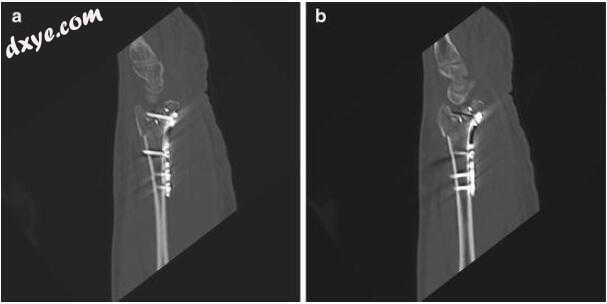

5.jpg

图3.5横向(a)和PA(b)观察状态 - 修复后固定与背侧尺骨板的放置。 注意关节面的尺寸方面的对齐和改善的支撑的恢复